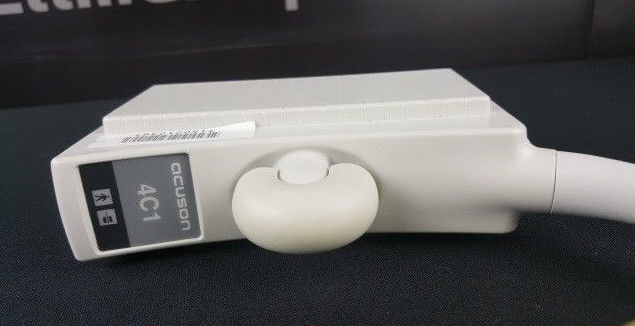

Acuson Probes

Showing 313 - 336 of 729 products